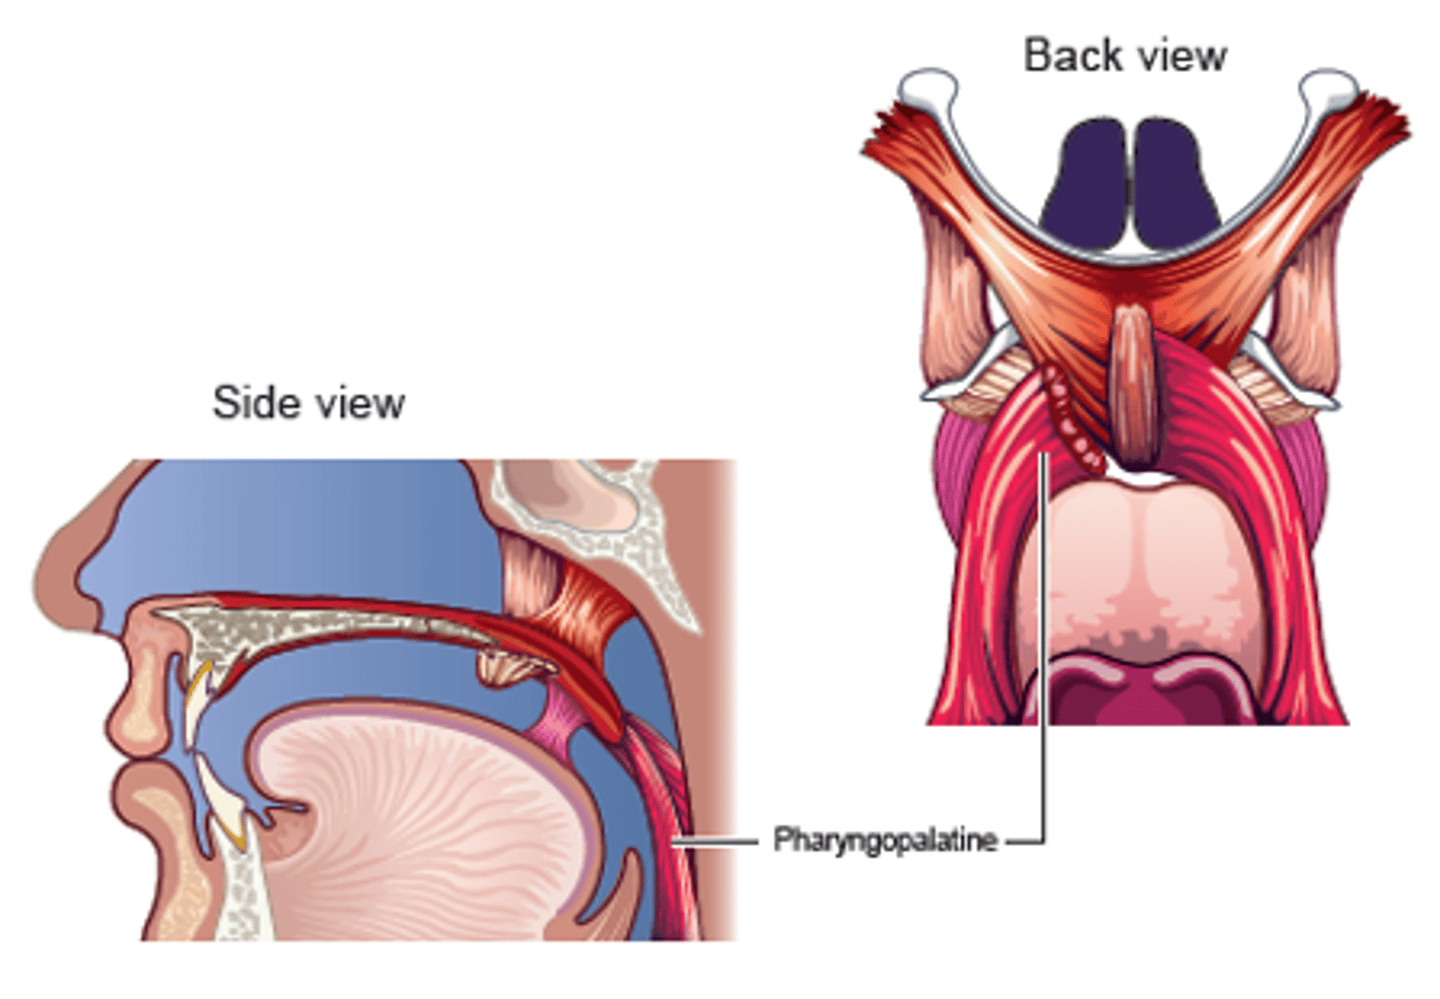

Palatopharyngeus Description

Also known as Pharyngopalatine

Posterior faucial pillar

- Longer muscle

Origin

- Soft palate

Course

- Superior through posterior faucial pillar

Insertion

- Lateral walls of pharynx, thyroid cartilage

Action

- Principally to guide material through pharynx

- May contribute to palatal lowering

- May contribute to VP seal

Palatopharyngeus Figure